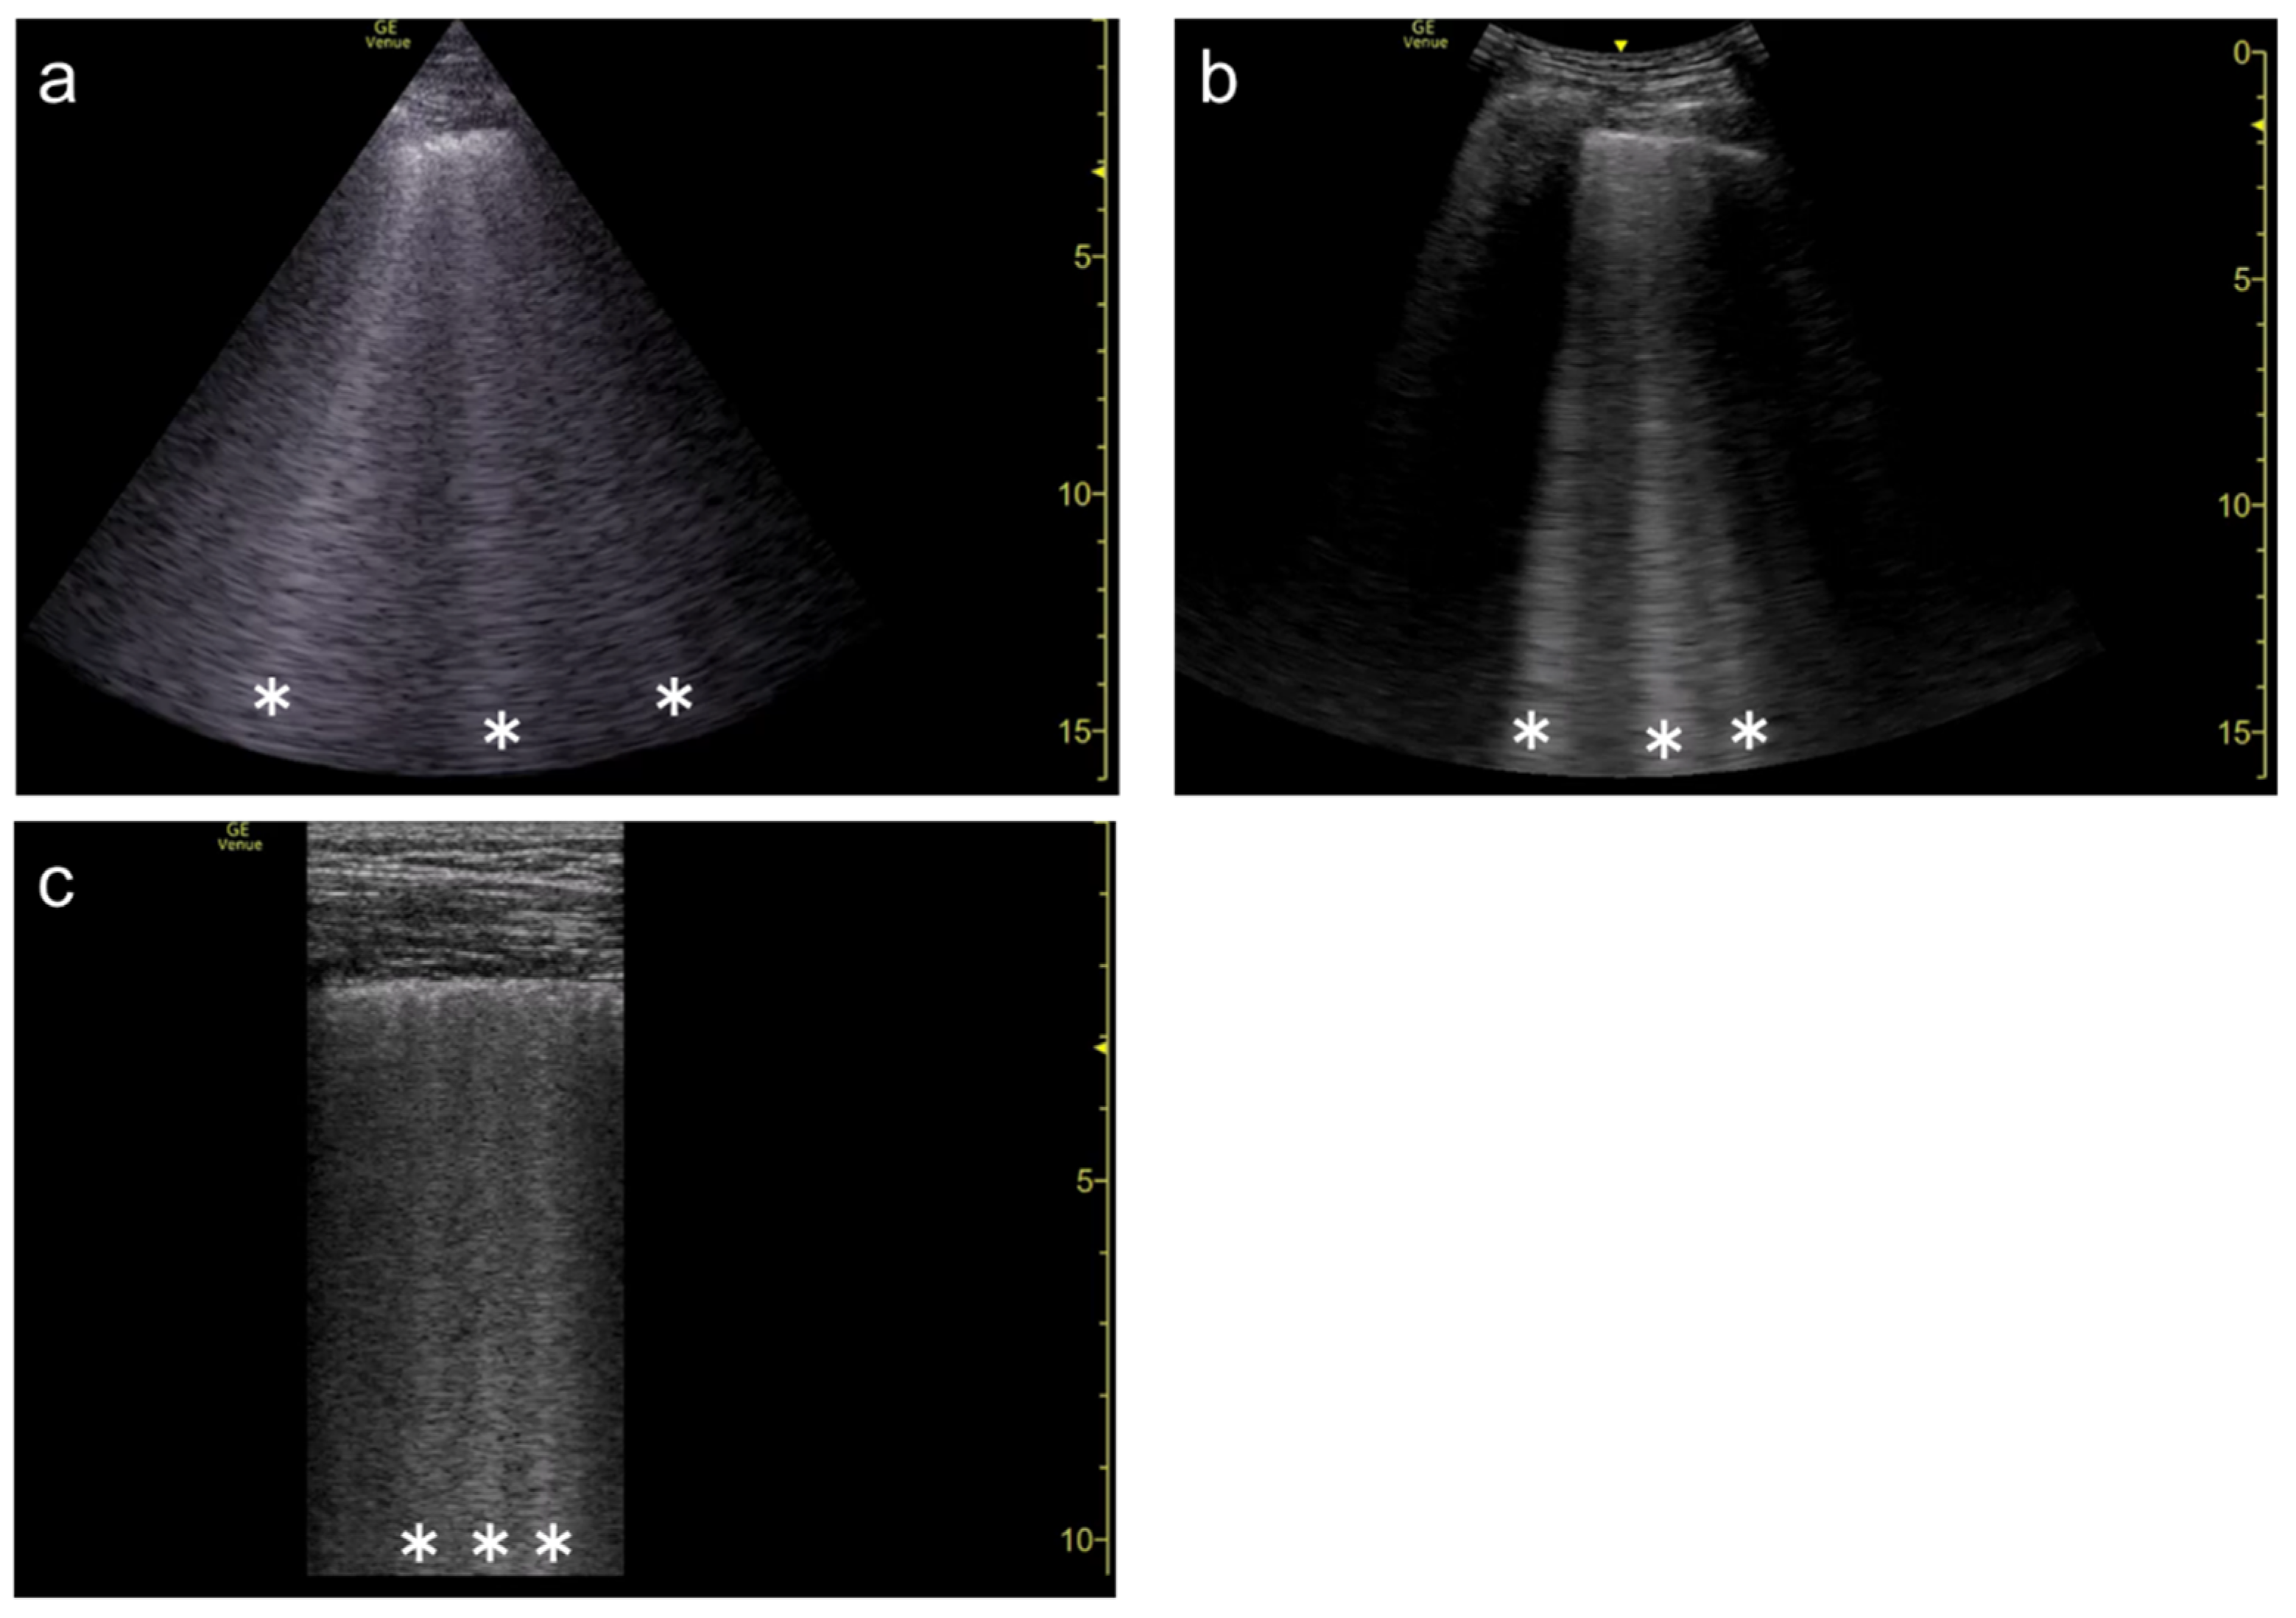

3.3. Frequency

3.4. Selection of Transducers